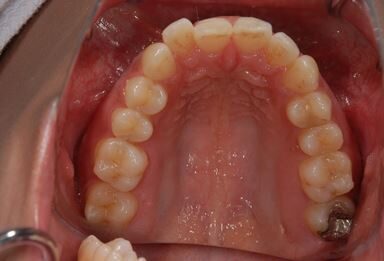

| 性別/年齢 | 女性 / 30歳 | ||||||||||||||||||||||||||||||||

| 主訴 | 銀歯がはずれた奥歯にひびが入っており、抜歯しなければいけないため、インプラントの治療相談を希望。 | ||||||||||||||||||||||||||||||||

| 治療内容 | インプラント1本、メタルボンドセラミック1本 | ||||||||||||||||||||||||||||||||

| 総治療費 | 401,363円 | ||||||||||||||||||||||||||||||||

| 治療期間 | 5ヶ月 |